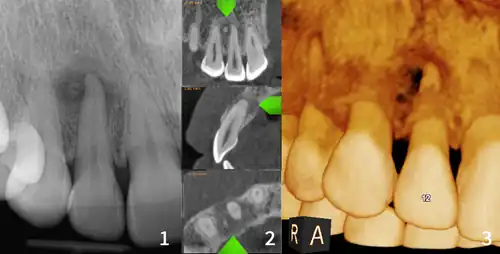

| Florid osseous dysplasia of the mandible | |

| Diagnostic method | X-ray, CBCT scan, vitality testing of teeth |

Cemento-osseous dysplasia (COD) is a benign condition of the jaws that may arise from the fibroblasts of the periodontal ligaments. It is most common in African-American females. The three types are periapical cemental dysplasia (common in those of African descent), focal cemento-osseous dysplasia (Caucasians), and florid cemento-osseous dysplasia (African descent). Periapical occurs most commonly in the mandibular anterior teeth while focal appears predominantly in the mandibular posterior teeth and florid in both maxilla and mandible in multiple quadrants.

Diagnosis is important so that the treating doctor does not confuse it for another periapical disease such as rarefying osteitis or condensing osteitis. Incorrect diagnosis could lead to unnecessary root canal treatments. It can be diagnosed by radiographic appearance. Confirming the tooth is vital, as is noting the demographic (African American females).[1][2][3]